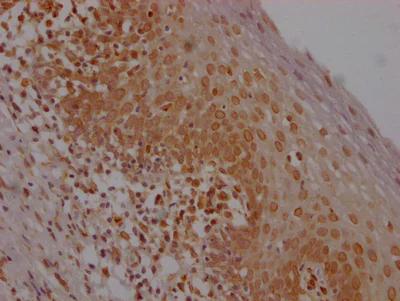

Immunohistochemistry (Formalin/PFA-fixed paraffin-embedded sections) - Anti-E2F1 antibody [1D12] (AB288369)

IHC image of ab288369 diluted at 1 : 100 and staining in paraffin-embedded human breast cancer performed on a Leica Bond™ system. After dewaxing and hydration, antigen retrieval was mediated by high pressure in a citrate buffer (pH 6.0). Section was blocked with 10% normal goat serum 30 min at RT. Then primary antibody (1% BSA) was incubated at 4°C overnight. The primary is detected by a Goat anti-rabbit IgG polymer labeled by HRP and visualized using 0.05% DAB.